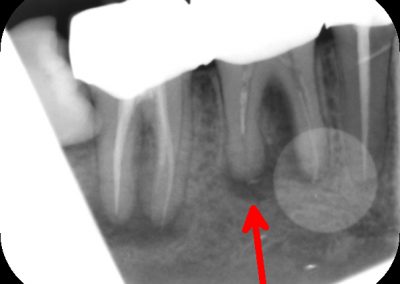

During the consultation, the dentist will first listen to your concerns and carry out appropriate tests to identify the right tooth that is causing pain. As a part of the diagnosis, your dentist will carry out various clinical tests to identify the right tooth and will take some radiographs which can aid in the diagnosis.

An access cavity is placed on the surface where the patient bites, to reach the root canals of the tooth. Once all the canals are identified, small files are used to remove the infected pulp.

Files of different sizes are used to eliminate bacteria and infection and to shape the canals. The canals are disinfected thoroughly with irrigants and later the canals will be sealed in 3 dimensions with a special medicament called gutta-percha to prevent reinfection of the tooth and the access cavity will be sealed with a temporary filling.